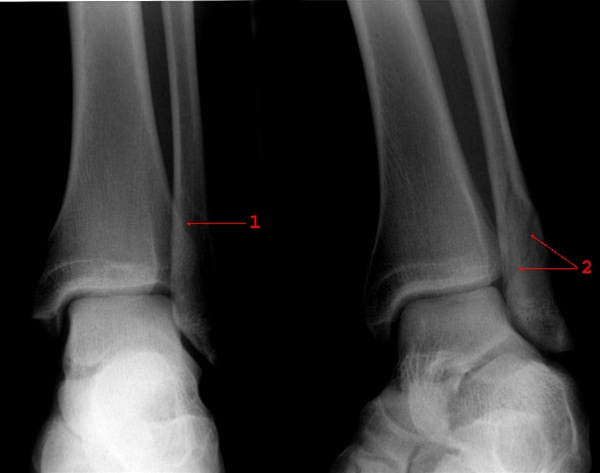

Forfra- og skråprojektion af venstre ankel. Skråfraktur (1 og 2), uden fejlstilling gennem laterale malleol. Frakturen er mest synlig i skråprojektion (2).